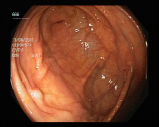

Endoscopies are used to detect diseases in the human digestive system. Images from inside the gastrointestinal tract can help physicians detect diseases early. The used dataset 777https://www.kaggle.com/datasets/abdallahwagih/kvasir-dataset-for-classification-and-segmentation contains eight image categories of the digestive system obtained through the endoscopy imaging technique, as shown in Fig. 8. There are a total of images that can be used in training and testing ML algorithms.